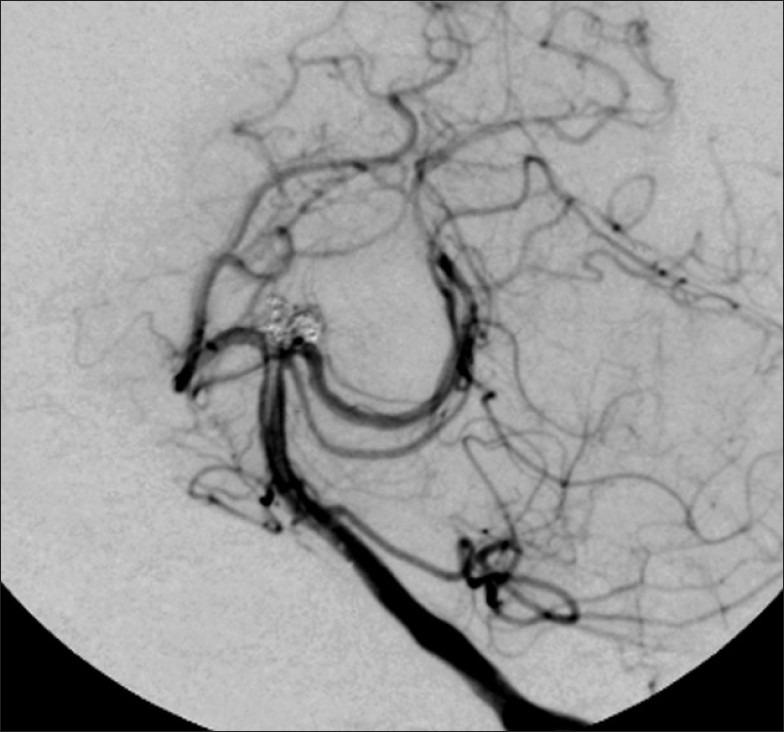

We developed a new 6-Fr guiding catheter (Slim Guide(®)) that features a large lumen (0.072 inch) for performing advanced techniques as are required in patients with wide-necked aneurysms whose treatment with a single microcatheter is difficult.

The Slim Guide was used to address 30 saccular and 20 dissecting aneurysms. All 50 patients presented with subarachnoid hemorrhage. To perform the advanced techniques we used SL-10(®) or Excel 14(®) and Hyperform(®) balloon microcatheters.

Of the 30 patients with saccular aneurysms, 20 were treated with the double microcatheter- and the other 10 with the balloon assist technique. All 20 patients with dissecting aneurysms were treated with the double microcatheter technique. We encountered slight interference during the treatment of one saccular aneurysm with the balloon assist technique using the Slim Guide guiding catheter; another patient with a saccular aneurysm treated with the balloon assist technique suffered a minor transient ischemic complication.

With the Slim Guide, the risks inherent in the application of advanced techniques may be decreased. Its use facilitates the coil embolization of aneurysms that pose treatment challenges.